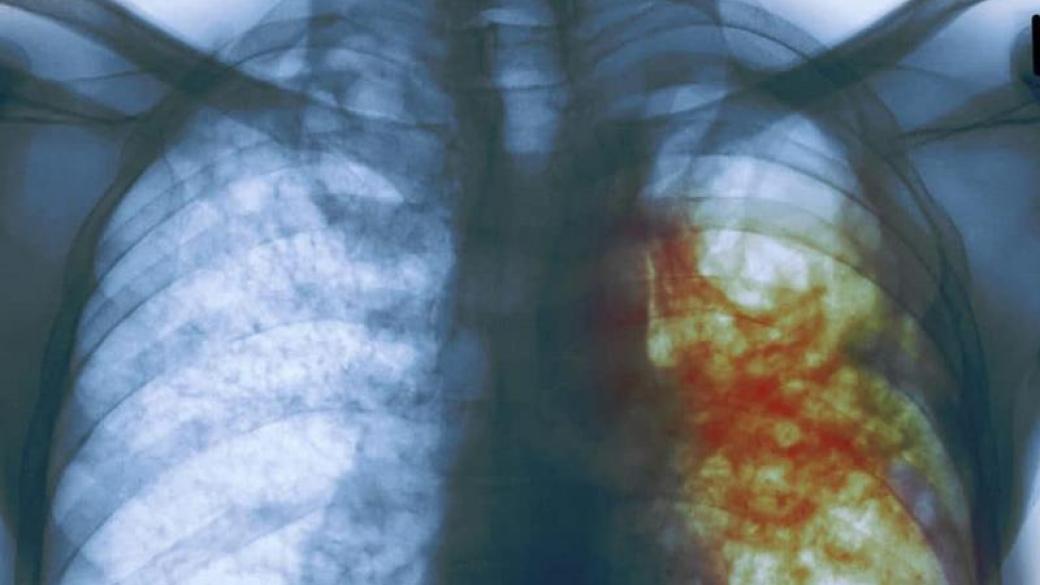

Министр здравоохранения Украины Максим Степанов считает, что последствием оптимизации в сфере медицины, предусмотренная вторым этапом реформы, может стать вспышка туберкулеза в стране. Об этом он заявил в ходе брифинга.

Министр уточнил, что прирост больных туберкулезом может составить 30%:

«Это не оптимизация, а банальное сокращение. Последствия будут такие, если мы сейчас не остановим этот процесс: как минимум, мы получим через 2−3 года рост заболеваемости на туберкулез на 30%. Увеличится и процент смертей из-за сокращения медработников, речь идет о тысячах медиков».

Степанов отметил, что в ближайшие дни попытается найти решение, как будут финансироваться противотуберкулезные диспансеры. На данный момент ситуация критическая — многим учреждениям не хватает до 80% необходимых денежных средств.